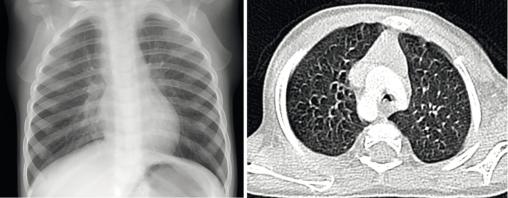

Radio du thorax et scanner thoracique revelant un double arc aortique compressif. Il s'agit d'une anomalie cardiaque fœtale responsable de compression trachéobronchique et/ou œsophagienne.